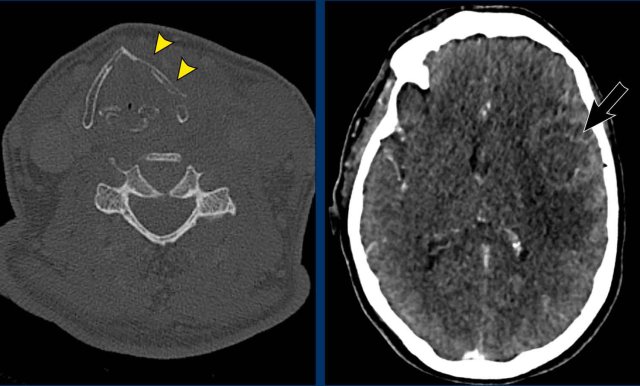

Case

Images of a patient with a rapidly enlarging neck mass, who complaints of swallowing problems and hoarseness.

The physical examination also detected a partial Horner with ptosis and miosis.

Images

CT of the head and neck shows an invasive thyroid mass with paralaryngeal and prevertebral extension and involvement of thyroid cartilage (yellow arrowhead).

There is a tumor thrombus in the jugular vein (black arrow).

Continue with the next images...

Notice the invasion of the thyroid cartilage (yellow arrowhead).

On the edge of the scan there was a brain metastasis.

Discusson

The Horner is caused by influencing the preganglionic system.

There are numerous fibers connecting the middle cervical ganglion (MCG) and inferior cervical ganglion (ICG), which are located anterior and posterior to the vertebral artery.

Final diagnosis

Anaplastic thyroid carcinoma.

This cancer is one of the most aggressive tumors and has a bad prognosis.